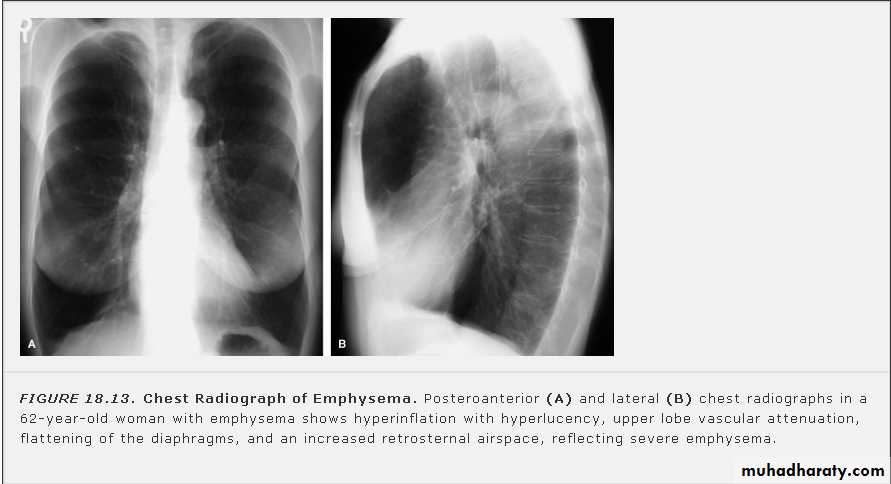

On a posteroanterior chest x-ray (A), the left hemithorax is very dark or lucent because the left lung has collapsed completely (white arrows).The tension pneumothorax can be identified because the mediastinal contents, including the heart, are shifted toward the right, and the left hemidiaphragm is flattened and depressed. A computed tomography scan done on a different patient with a tension pneumothorax (B) shows a completely collapsed right lung (arrows) and shift of the mediastinal contents to the left.

Tension Pneumothorax. Portable chest film in a 43-year-old woman with ARDS shows a large right pneumothorax with mediastinal shift and ipsilateral diaphragmatic depression, suggesting tension.

Air was evacuated under pressure during emergent placement of a right chest tube.